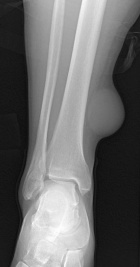

49 year old male with slow growing cystic mass over distal aspect right leg.

Zoom image: Radiological image Radiological image.